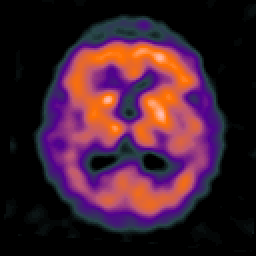

Alzheimer's disease: overlay -- Slice #14

[Home][Help][Clinical] Slice 14